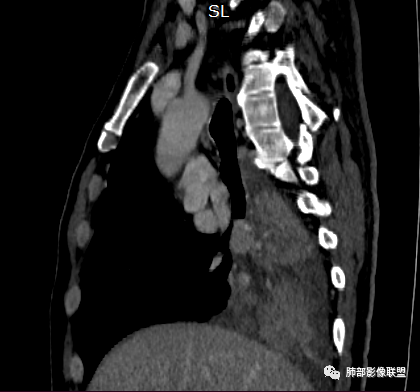

冠状位重建有钻缝的感觉

南边:

粘液腺不符合

粘液腺是外围朝内推移的

不应该近端腔内结节强化明显

我再发一些图

这是源头

这些如果单纯不张肯定强化明显